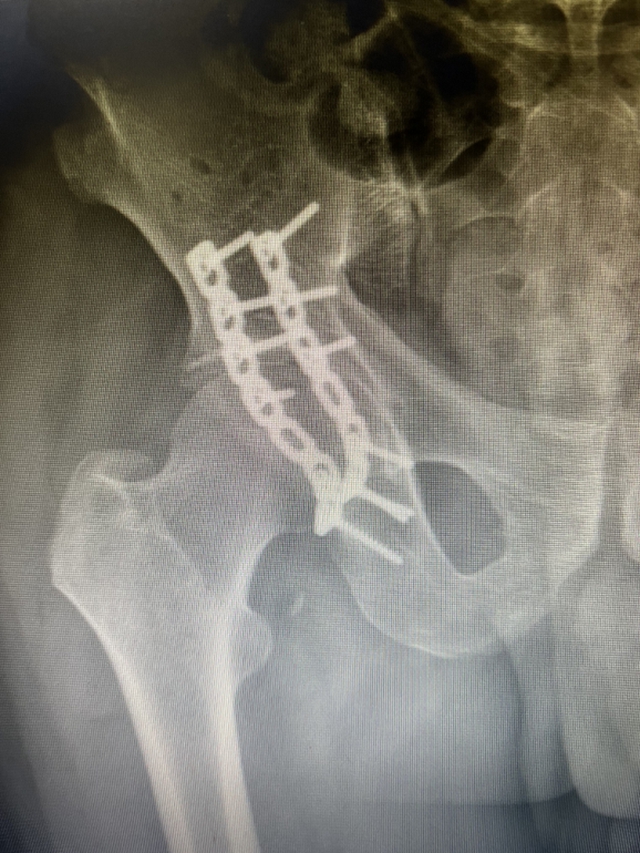

经过精心准备,黄陈翼于8月8日给杨大爷进行了手术治疗,手术非常成功,目前在进行后期康复治疗,杨大爷的子女也可以在一旁精心照顾。

据骨伤科创伤·正骨组主任刘宗超教授介绍:该患者为髋臼粉碎性骨折,为骨伤科常见骨折,该骨折如果处理不当会造成严重的关节功能障碍。近几年,科室接收治疗该类患者约500例以上,已掌握非常丰富的治疗经验。

骨伤科创伤·正骨组秉承 “中西合璧,筋骨并重,动静结合,医患携手”的理念,以“骨折(手术)微创,中医(正骨)特色,科研创新、人才尽用”为发展模式,开展了四肢骨折、脱位的经典中医治疗(手法复位、撬拨复位、夹板固定)及微创手术(计算机辅助导航下骨盆、髋臼通道螺钉内固定术、闭合复位髓内钉内固定技术、微创钢板置入内固定技术等),尤其针对四肢开放性骨折、骨感染、骨不连等棘手疑难病例有独到见解,开展了骨诱导膜技术(Masquelet) 、骨搬运技术、带血管蒂肌骨瓣移植术、大段骨缺损3D打印假体及同种异体骨移植术等治疗手段;近几年科室紧跟科技发展步伐,将牵引架辅助顺势牵引技术、3D打印技术,计算机辅助导航技术等精准医学技术应用于创伤骨科领域,减小手术创伤、提高疾患疗效、缩短住院时间、节省治疗费用。